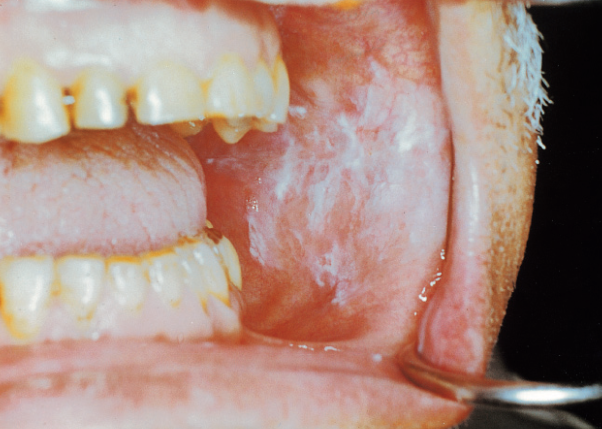

**점액낭종(Mucocele)**은 입안의 **작은 침샘(소타액선)**이 손상되어 점액이 조직 내에 고이면서 생기는 무통성 물혹입니다.

항목 내용 발생 부위 입술 안쪽, 혀 밑, 뺨 안쪽 점막 등 색상 투명~흰색, 연보라색 또는 약간 파란빛 촉감 말랑말랑하고 부드럽지만 눌러도 아프지 않음 크기 보통 0.5cm~1.5cm, 커지기도 함 👉 겉으로는 수포나 궤양처럼 보일 수 있어 오해하기 쉽지만, 점액낭종은 염증이나 바이러스성 감염과는 다릅니다.